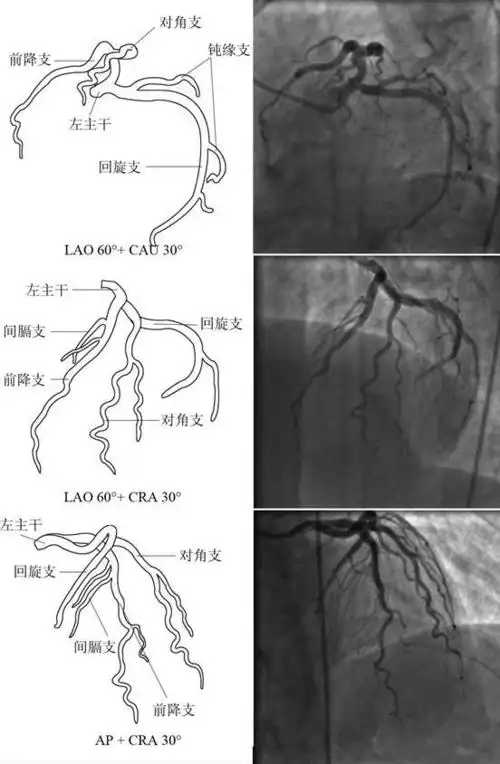

冠状动脉狭窄的血管造影

冠状动脉造影